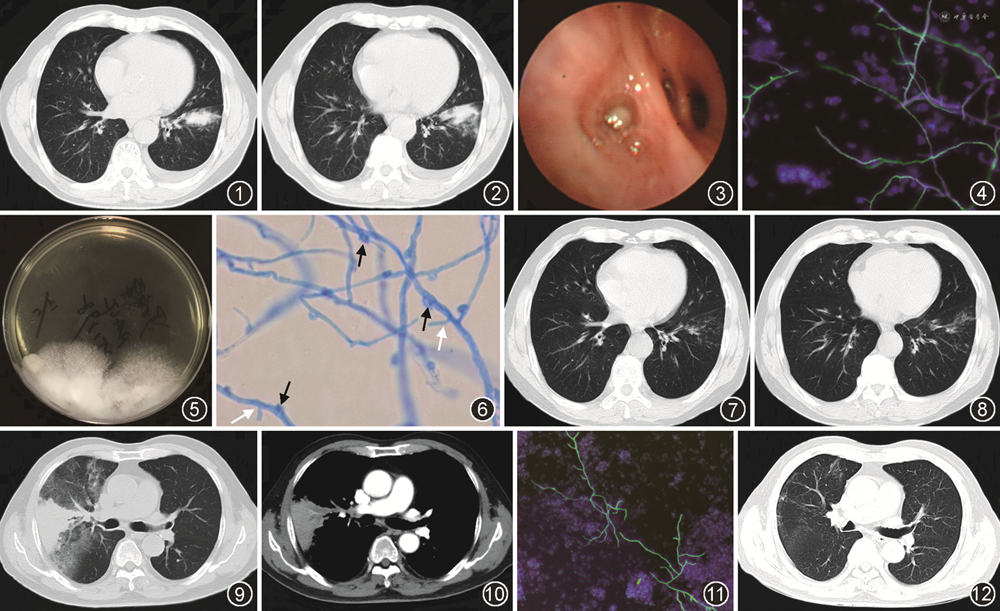

例1 患者男,73岁,因“体检发现肺结节1个月,左下胸痛1 d”于2018年11月入院。1个月前患者体检时查胸部CT提示左肺下叶前内基底段结节,无发热,无咳嗽咳痰,无胸闷气促,无胸痛等不适,遂至当地医院就诊,予“阿莫西林克拉维酸联合阿奇霉素”抗感染治疗2周,复查胸部CT提示病灶无变化,行经皮肺穿刺活检病理提示支气管黏膜及少量肺组织,见肺组织纤维化伴较多淋巴细胞及组织细胞浸润。肺穿刺活检组织感染病原学宏基因组测序(metagenomic next-generation sequencing,mNGS)检测到铜绿假单胞菌,检出序列数7,当时未行相关抗铜绿假单胞菌治疗。1 d前出现左下胸痛,深呼吸及咳嗽时加重,于当地医院复查胸部CT示左肺下叶片状高密度影,较前增大,左侧少量胸腔积液(图1,2),遂来我院就诊,以“肺占位性质待查”入院。患者既往无支气管哮喘病史,有长期种植花草史30余年(卧室阳台及院中均种植花草)。入院体检:生命体征平稳,双肺呼吸音粗,未闻及干湿性啰音,心腹及神经系统未见异常,双下肢无水肿。入院查血常规及C反应蛋白示白细胞计数8.2×109/L,嗜酸粒细胞计数0.28×109/L,中性粒细胞百分比84.8%,C反应蛋白8.5 mg/L,肿瘤标志物CA-125为105.3 U/ml(正常参考值<35.0 U/ml),余肿瘤标志物未见异常。总IgE为180 U/ml(正常参考值<165 U/ml),类风湿因子、补体C3及补体 C4、免疫球蛋白、抗核抗体、血管炎均阴性。多次痰涂片抗酸染色阴性,支气管肺泡灌洗液(BALF)涂片抗酸染色阴性,BALF结核分枝杆菌核酸和利福平耐药突变(Xpert MTB/RIF)阴性。血清及BALF隐球菌荚膜多糖抗原阴性,血清1,3-β-D葡聚糖(G试验)50 ng/L(正常参考值<70 ng/L),BALF半乳糖甘露醇聚糖抗原(GM试验)为0.07 μg/L,血清烟曲霉IgG为440 AU/ml(正常参考值<120 AU/ml),血清烟曲霉IgE<0.1 U/ml(正常参考值<0.35 U/ml),支气管镜检查见左下叶内前基底段(B7+8)黏膜充血水肿,开口见痰黏液栓(图3)。经支气管镜肺活检病理示纤维化组织内见急慢性炎症细胞浸润,局灶肺泡上皮细胞轻度不典型增生。BALF真菌涂片及真菌荧光染色涂片见丝状真菌菌丝(图4),BALF培养生长出多个白色绒毛状菌落(图5),菌落压片后菌丝可见锁状结构和针状结构(图6),外送内转录间隔区(internal transcribed spacer,ITS)区域DNA测序显示,ITS基因扩增可见单一清晰目的条带,测序结果经BLAST(basic local alignment search tool)对比显示与普通裂褶菌序列相似度为100%,诊断为肺普通裂褶菌感染。给予伏立康唑(200 mg,2次/d)治疗1个月后复查胸部CT示左肺下叶团块影基本吸收(图7,8),总疗程4个月后停药随访,但于2021年7月出现左下新发病灶(B9亚段),BALF真菌涂片及培养再次证实肺普通裂褶菌感染,使用伏立康唑(200 mg,2次/d)治疗2个月余后自行停药,复查胸部CT示病灶较前吸收,目前情况良好,无不适。

例2 患者男,83岁,因“咳嗽、咳痰2个月”于2021年5月入院,患者于2个月前无明显诱因下出现咳嗽咳痰,咳白色黏痰,偶有咳嗽时伴气促,无发热、胸痛等不适,于当地医院查血常规示白细胞8.6×109/L,嗜酸粒细胞数为0.9×109/L及胸部CT示右肺上叶楔形状高密度影伴周围渗出影,双肺上叶纤维化病灶伴局部轻度支气管扩张,予“哌拉西林他唑巴坦联合左氧氟沙星”抗感染治疗10 d,但症状未见缓解,复查胸部CT示右肺上叶病灶较前明显进展,现患者咳嗽咳痰明显,夜间平卧时咳嗽加剧,时感气促不适,以“阻塞性肺炎”收入院。既往有支气管哮喘病史30余年,予布地奈德福莫特罗粉吸入剂(320 μg:9.0 μg)规律治疗,此次未有急性发作,有高血压病病史10余年,血压控制良好。体检:生命体征平稳,双肺呼吸音粗,双肺未闻及干湿性啰音,心腹及神经系统未见异常,双下肢无水肿。入院后查血常规及C反应蛋白示白细胞9.39 × 109/L,嗜酸粒细胞计数0.83× 109/L,中性粒细胞百分比69.7%,C反应蛋白126.6 mg/L,总IgE为5 U/ml,类风湿因子、补体C3及补体C4、免疫球蛋白、抗核抗体、血管炎均阴性。多次痰涂片抗酸染色阴性,BALF涂片抗酸染色阴性,BALF Xpert MTB/RIF阴性。血清及BALF隐球菌荚膜多糖抗原阴性,血清G试验56 ng/L,BALF GM试验0.15 μg/L,血清烟曲霉IgG 208 AU/ml,血清烟曲霉IgE 0.77 U/ml,行胸部增强CT示右肺上叶前段楔形团片状高密度影,周围可见明显渗出影,增强见血管造影征及低密度状分支状影(图9,10)。支气管镜检查见右上叶开口黏膜水肿、稍肥厚,前段支气管开口见黄白色黏稠胶冻样纵行痰栓,右上开口黏膜活检病理示支气管黏膜慢性炎,局部见炎性渗出物及少许真菌菌丝,特殊染色六胺银(+),真菌D-PAS(+),BALF真菌荧光染色涂片见丝状真菌菌丝(图11),外送ITS区域DNA测序显示ITS基因扩增可见单一清晰目的条带,测序结果经BLAST对比显示与普通裂褶菌序列相似度最高,为99.79%,诊断为肺普通裂褶菌感染,给予伏立康唑(200 mg,2次/d)治疗2个月余后于当地医院复查胸部CT示右肺上叶不张及周围渗出影基本吸收,留少许纤维条索影(图12)。继续治疗2个月(总疗程4个月)后停药随访,目前情况良好,无相关呼吸系统症状。